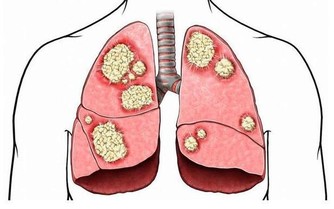

體重改變、常常口渴和想上廁所

這些表現有點像糖尿病,有必要去做血糖查看。假如查看成果還算正常,就要控制,少吃或不吃甜食和油膩的食物。